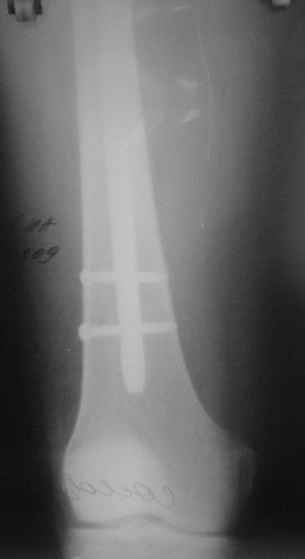

Перелом большеберцовой кости почти околосуставный, могут потребоваться дополнительные меры для восстановления оси (отклоняющие спицы или винты), и запирающих винтов в дистальный отломок желательно побольше. Задний край не сломан ли там, не разобрал по этим снимкам.